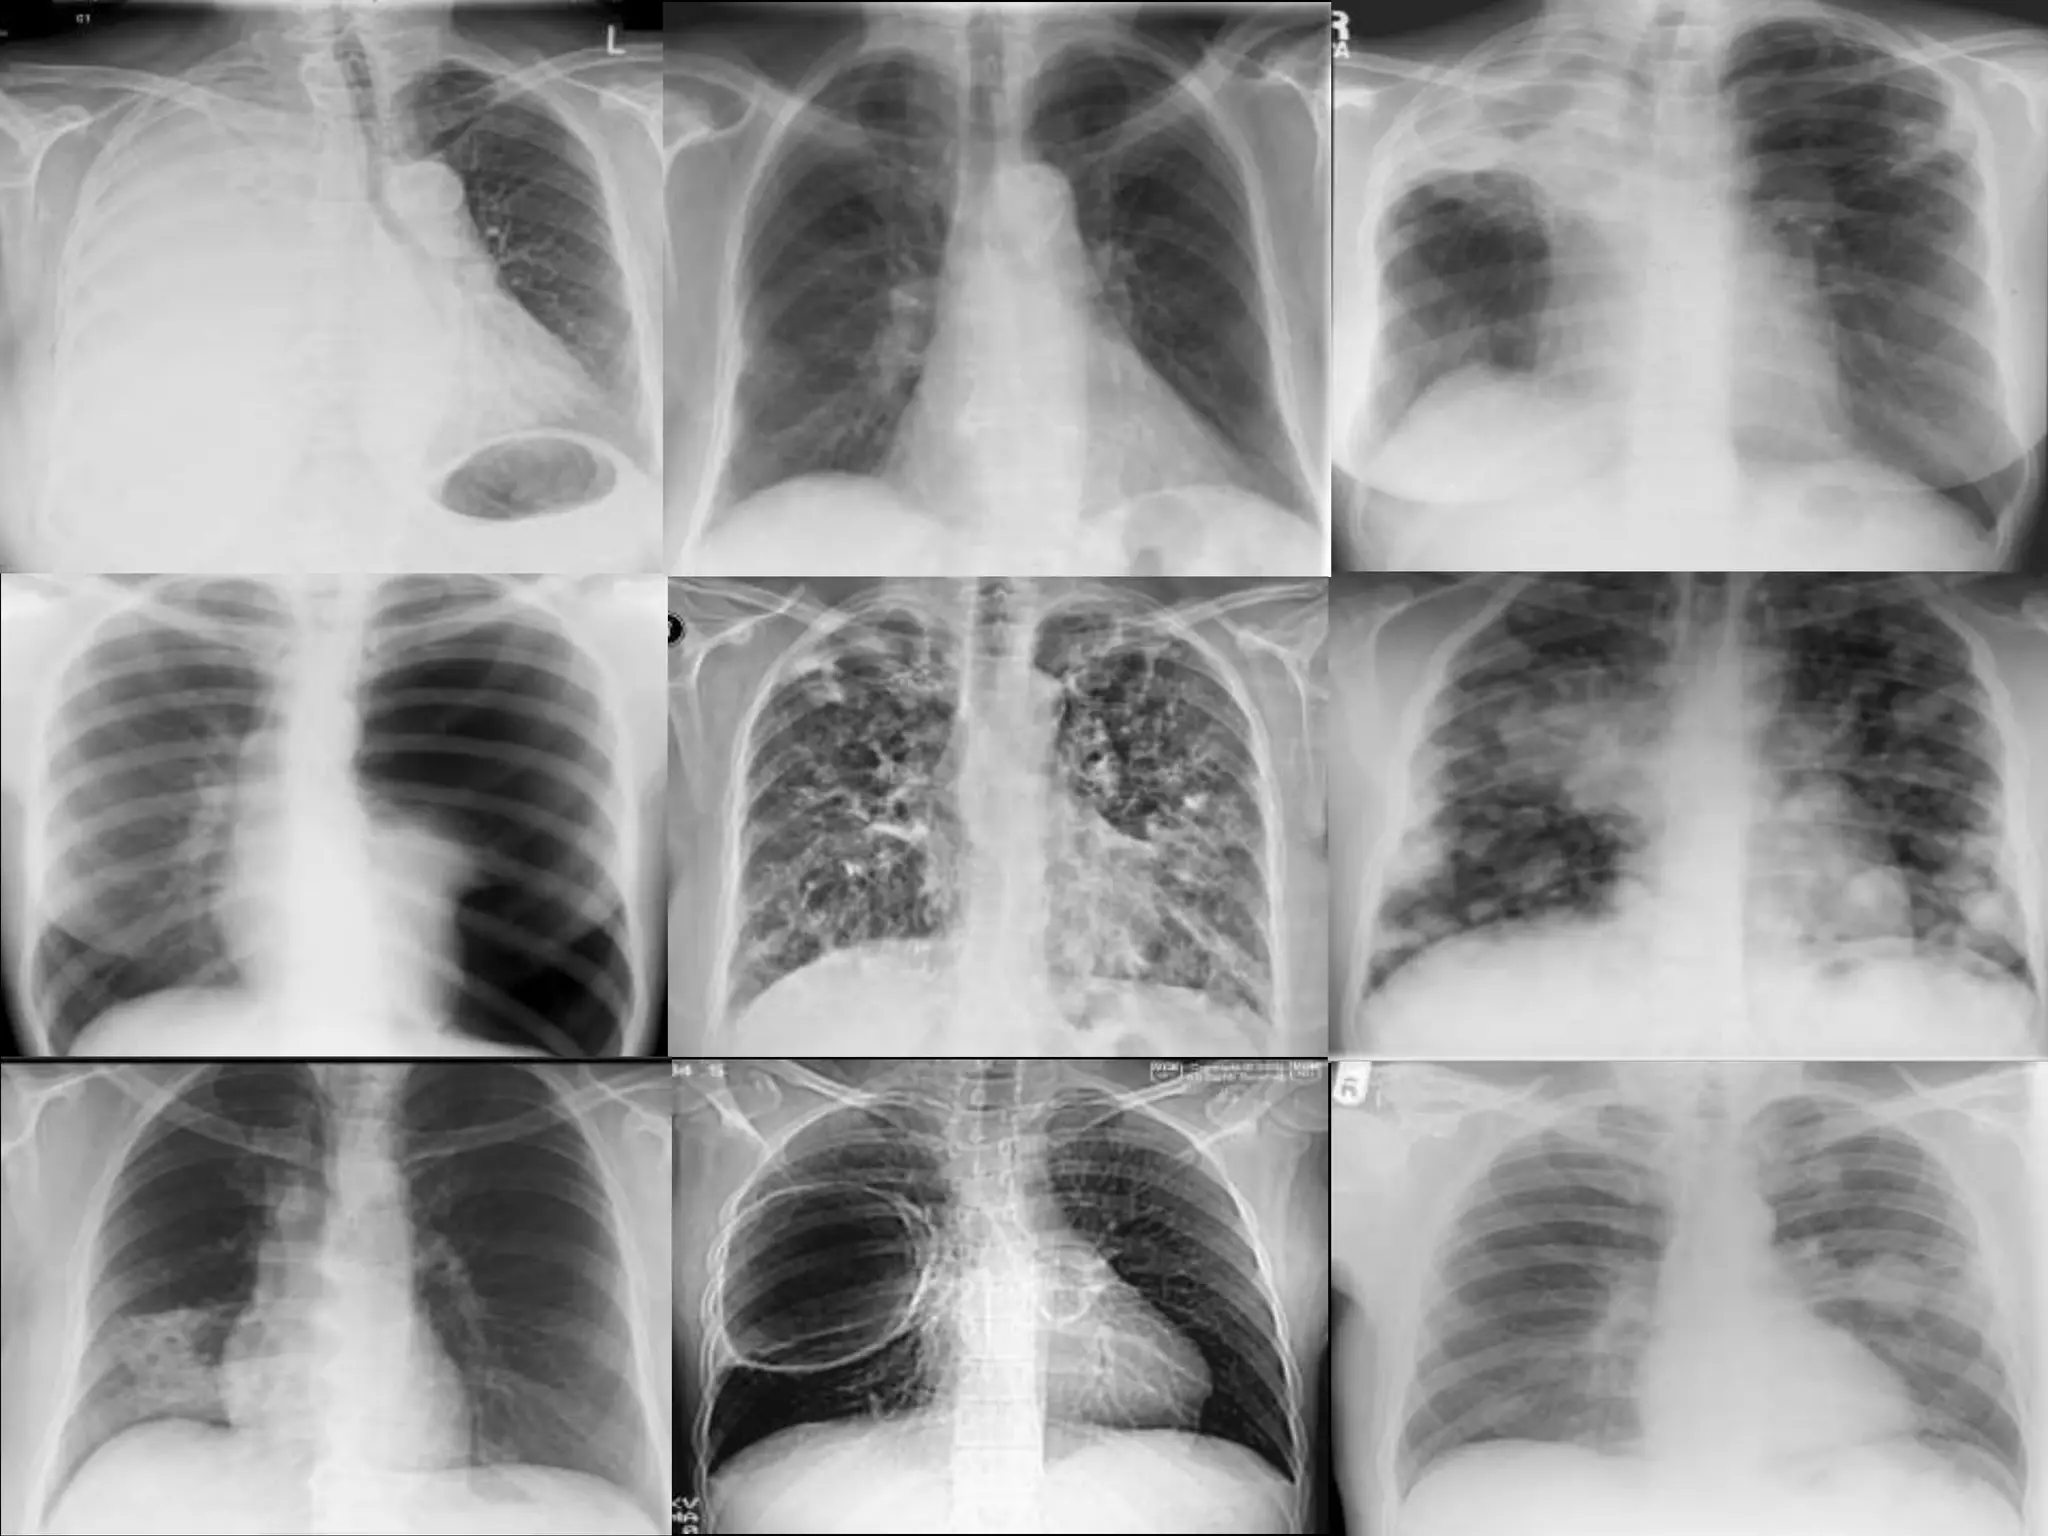

Este documento proporciona una lista de términos radiológicos relacionados con el tórax y los pulmones. Incluye descripciones breves de diferentes patrones de opacidad pulmonar como consolidación, neumotorax, nódulos y cavernas, así como sus posibles causas. También cubre términos relacionados con el mediastino y las técnicas de imagen torácica.